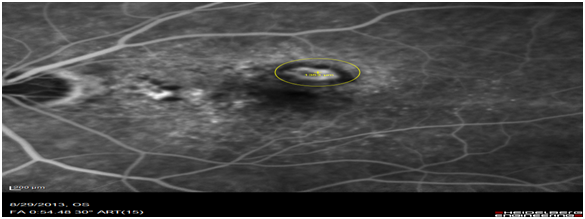

Images of patients (n=63) of patients who had classic type 2 CNV was retrospectively analysed. OCT images obtained on the Heidelberg spectral is at diagnosis were compared to the FFA images obtained on the same day. The OCT biomarker, the sub retinal hyper reflective mass (SRHRM) was used. The same photographer was used to minimise bias. The sub retinal hyper reflective mass was used as the OCT biomarker. The size of this SRHRM was measured at its widest using the caliper setting. This was then compared to the widest diameter of the CNV leakage measured on ultra high-resolution spectral is FFA by drawing a circle around the leage and noting its diameter (Figure 1A,1B & 2A,2B).

Figure 2B Measurement of CNV in the early phase on FFA scan (1355m).